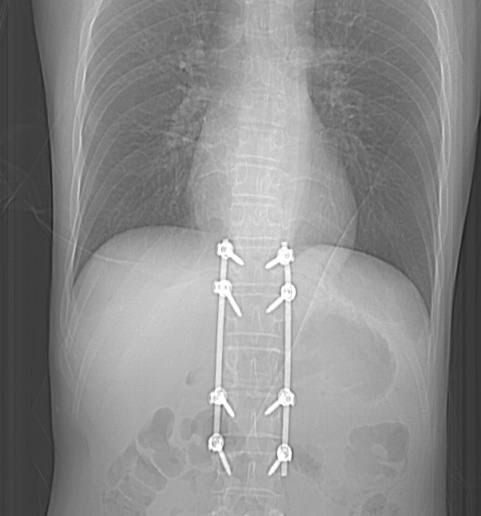

Медики также обнаружили и устранили у пациента повреждения желчевыводящих путей. Из-за этого пострадавшему удалили желчны пузырь и провели дренирование холедоха. Затем пострадавшему потребовалась операция на позвоночнике с транспедикулярной фиксацией.